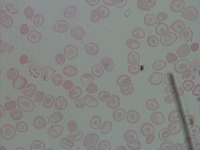

Medical Diagnosis and Research: The "New-Chula" model could be used in medical laboratories and hospitals to automatically identify and classify different cell types in blood samples. This could assist in diagnosing various blood disorders or diseases such as anemia or leukemia, thereby speeding up analysis and treatment processes.

Education and Training: The model could serve as an educational tool for medical students or professionals in training. By using this model, they could learn to identify various types of cells more quickly and accurately, enhancing their understanding of hematology.

Pharmaceutical Trials: During drug testing and development, pharmaceutical companies may use this model to analyze the impact of drugs on different cell types in order to assess effectiveness or side effects.

Public Health Monitoring: Governments and public health organizations could use it to monitor the health condition of the general population, potentially detecting the early stages of an outbreak or epidemic.

Biotechnology Industry: Biotech firms or research labs may use this model for particular research projects involving genetic modification or cellular biology studies where identification and classification of different cell types is necessary.